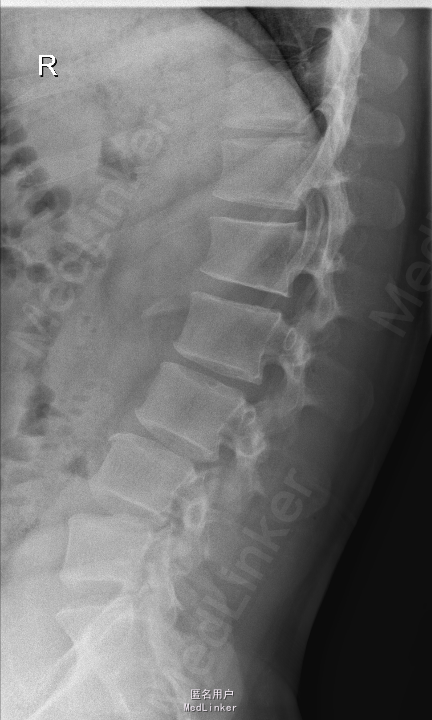

查体:腰部叩痛,腰部活动受限,左侧膝内侧、小腿外侧、内踝、足部感觉减退,右侧小腿、足背感觉减退,屈髋、伸膝、踝背伸肌肌力左侧4级,右侧4-5级,踇背伸、跖屈肌肌力左侧3-4级,右侧4级,双侧膝腱反射+,跟腱反射+,双侧巴氏征阴性,直腿抬高试验左侧40°阳性,右侧阴性。 辅助检查: X-ray:腰椎退行性变,多节段不稳 CT:腰椎间盘突出并椎管狭窄伴钙化,腰2-3,3-4,4-5,腰5骶1 MR:腰椎间盘突出并椎管狭窄,腰2-3,3-4,4-5,腰5骶1 上传受限无法全部上传,见谅

诊断:腰椎间盘突出症并椎管狭窄 处理: 1、完善相关辅助检查,明确诊断,有无手术指证; 2、完善手术评估,有无手术禁忌,手术风险及并发症; 3、在全麻下行腰椎后路多节段减压椎间植骨融合内固定术 4、腰2-3,腰3-4行开窗减压,腰4-5,腰5-骶1行椎间Cage植骨融合